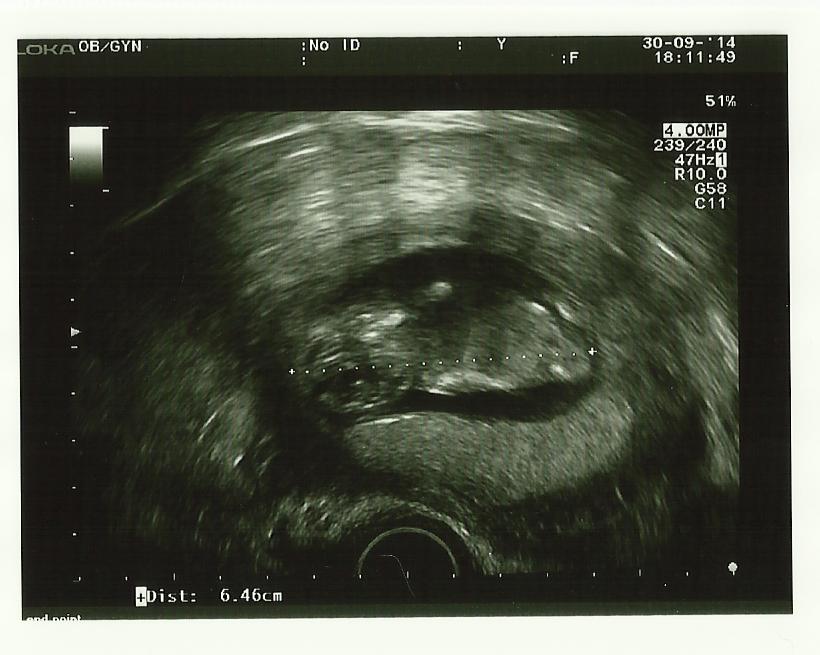

Op 30 september 2014 hadden papa en mama opnieuw een afspraak bij dokter Lampaert, de gynaecologe. Wat is het toch fijn om jou echt te kunnen zien… Ondertussen ben je al bijna 6.5 cm groot. Mama kon je deze keer niet zo goed zien bij de echo, maar papa genoot dan maar voor twee (echt waar). Je was deze keer trouwens heel beweeglijk… een echte salsera of salsero of toch een dressuurruitertje?